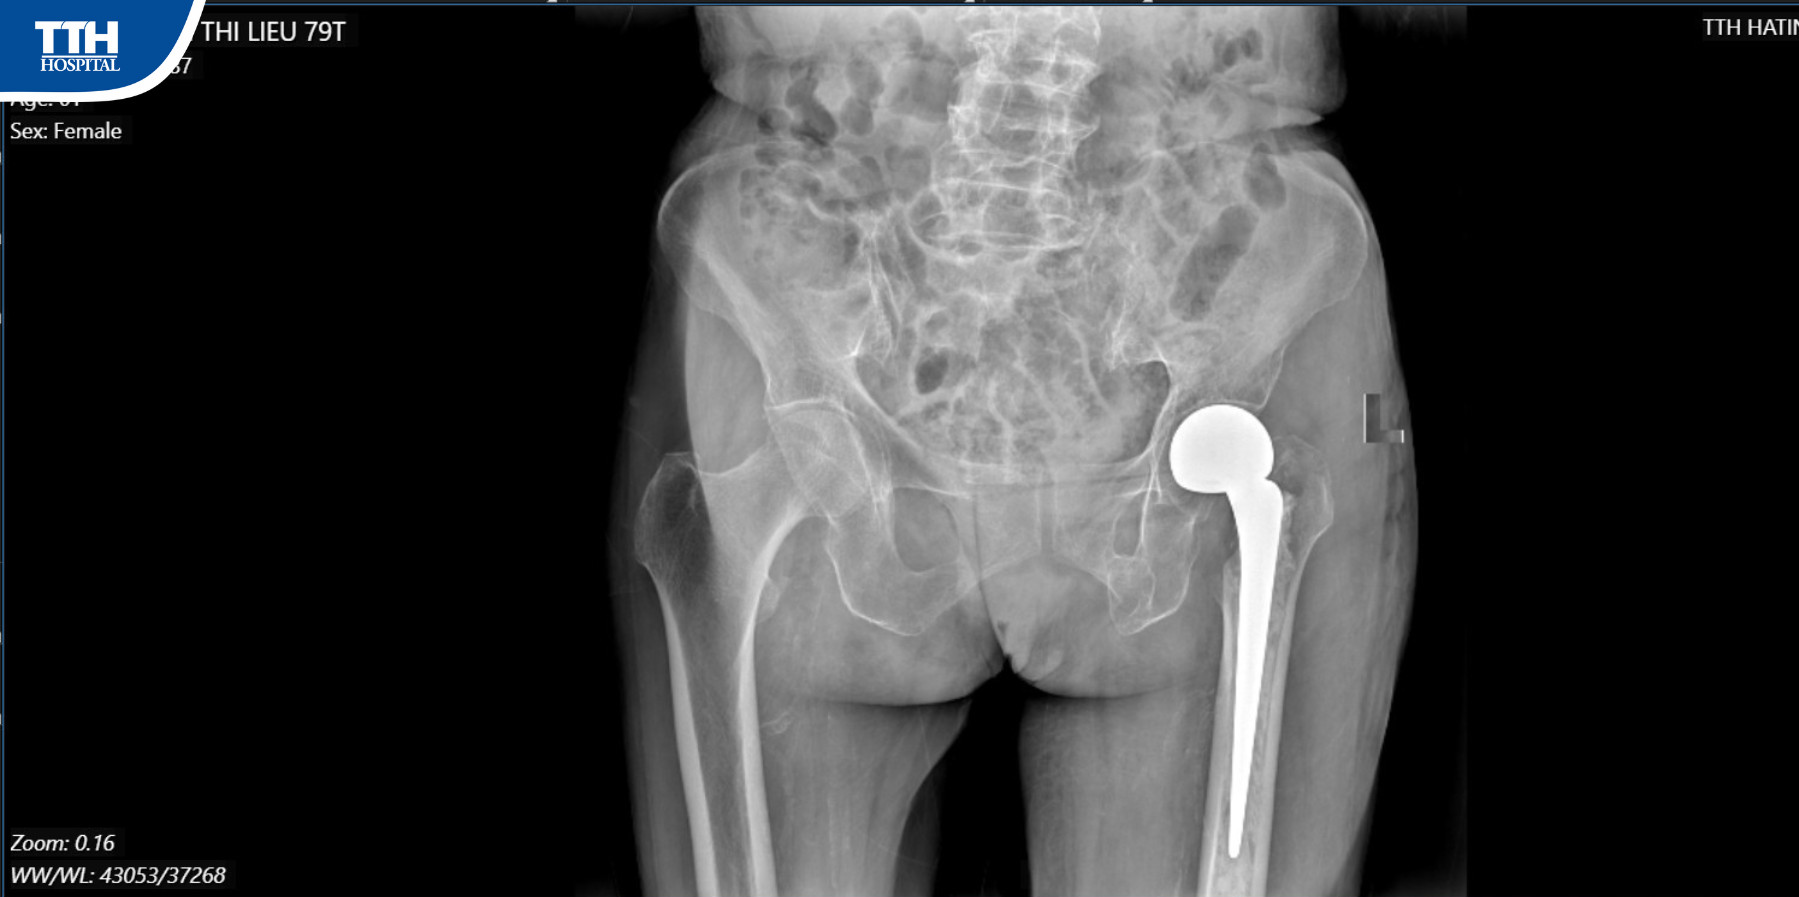

Điều trị gãy cổ xương đùi tùy thuộc vào loại gãy và độ tuổi bệnh nhân. Tuy nhiên, đối với người lớn tuổi và bị loãng xương, phương pháp hiệu quả nhất là thay khớp háng nhân tạo bán phần có xi măng”.

Sau 4 ngày phẫu thuật bệnh nhân đã đi lại được, tỉnh táo, ăn uống bình thường, bớt đau nhức và đã được các Bác sĩ hướng dẫn tập phục hồi chức năng.